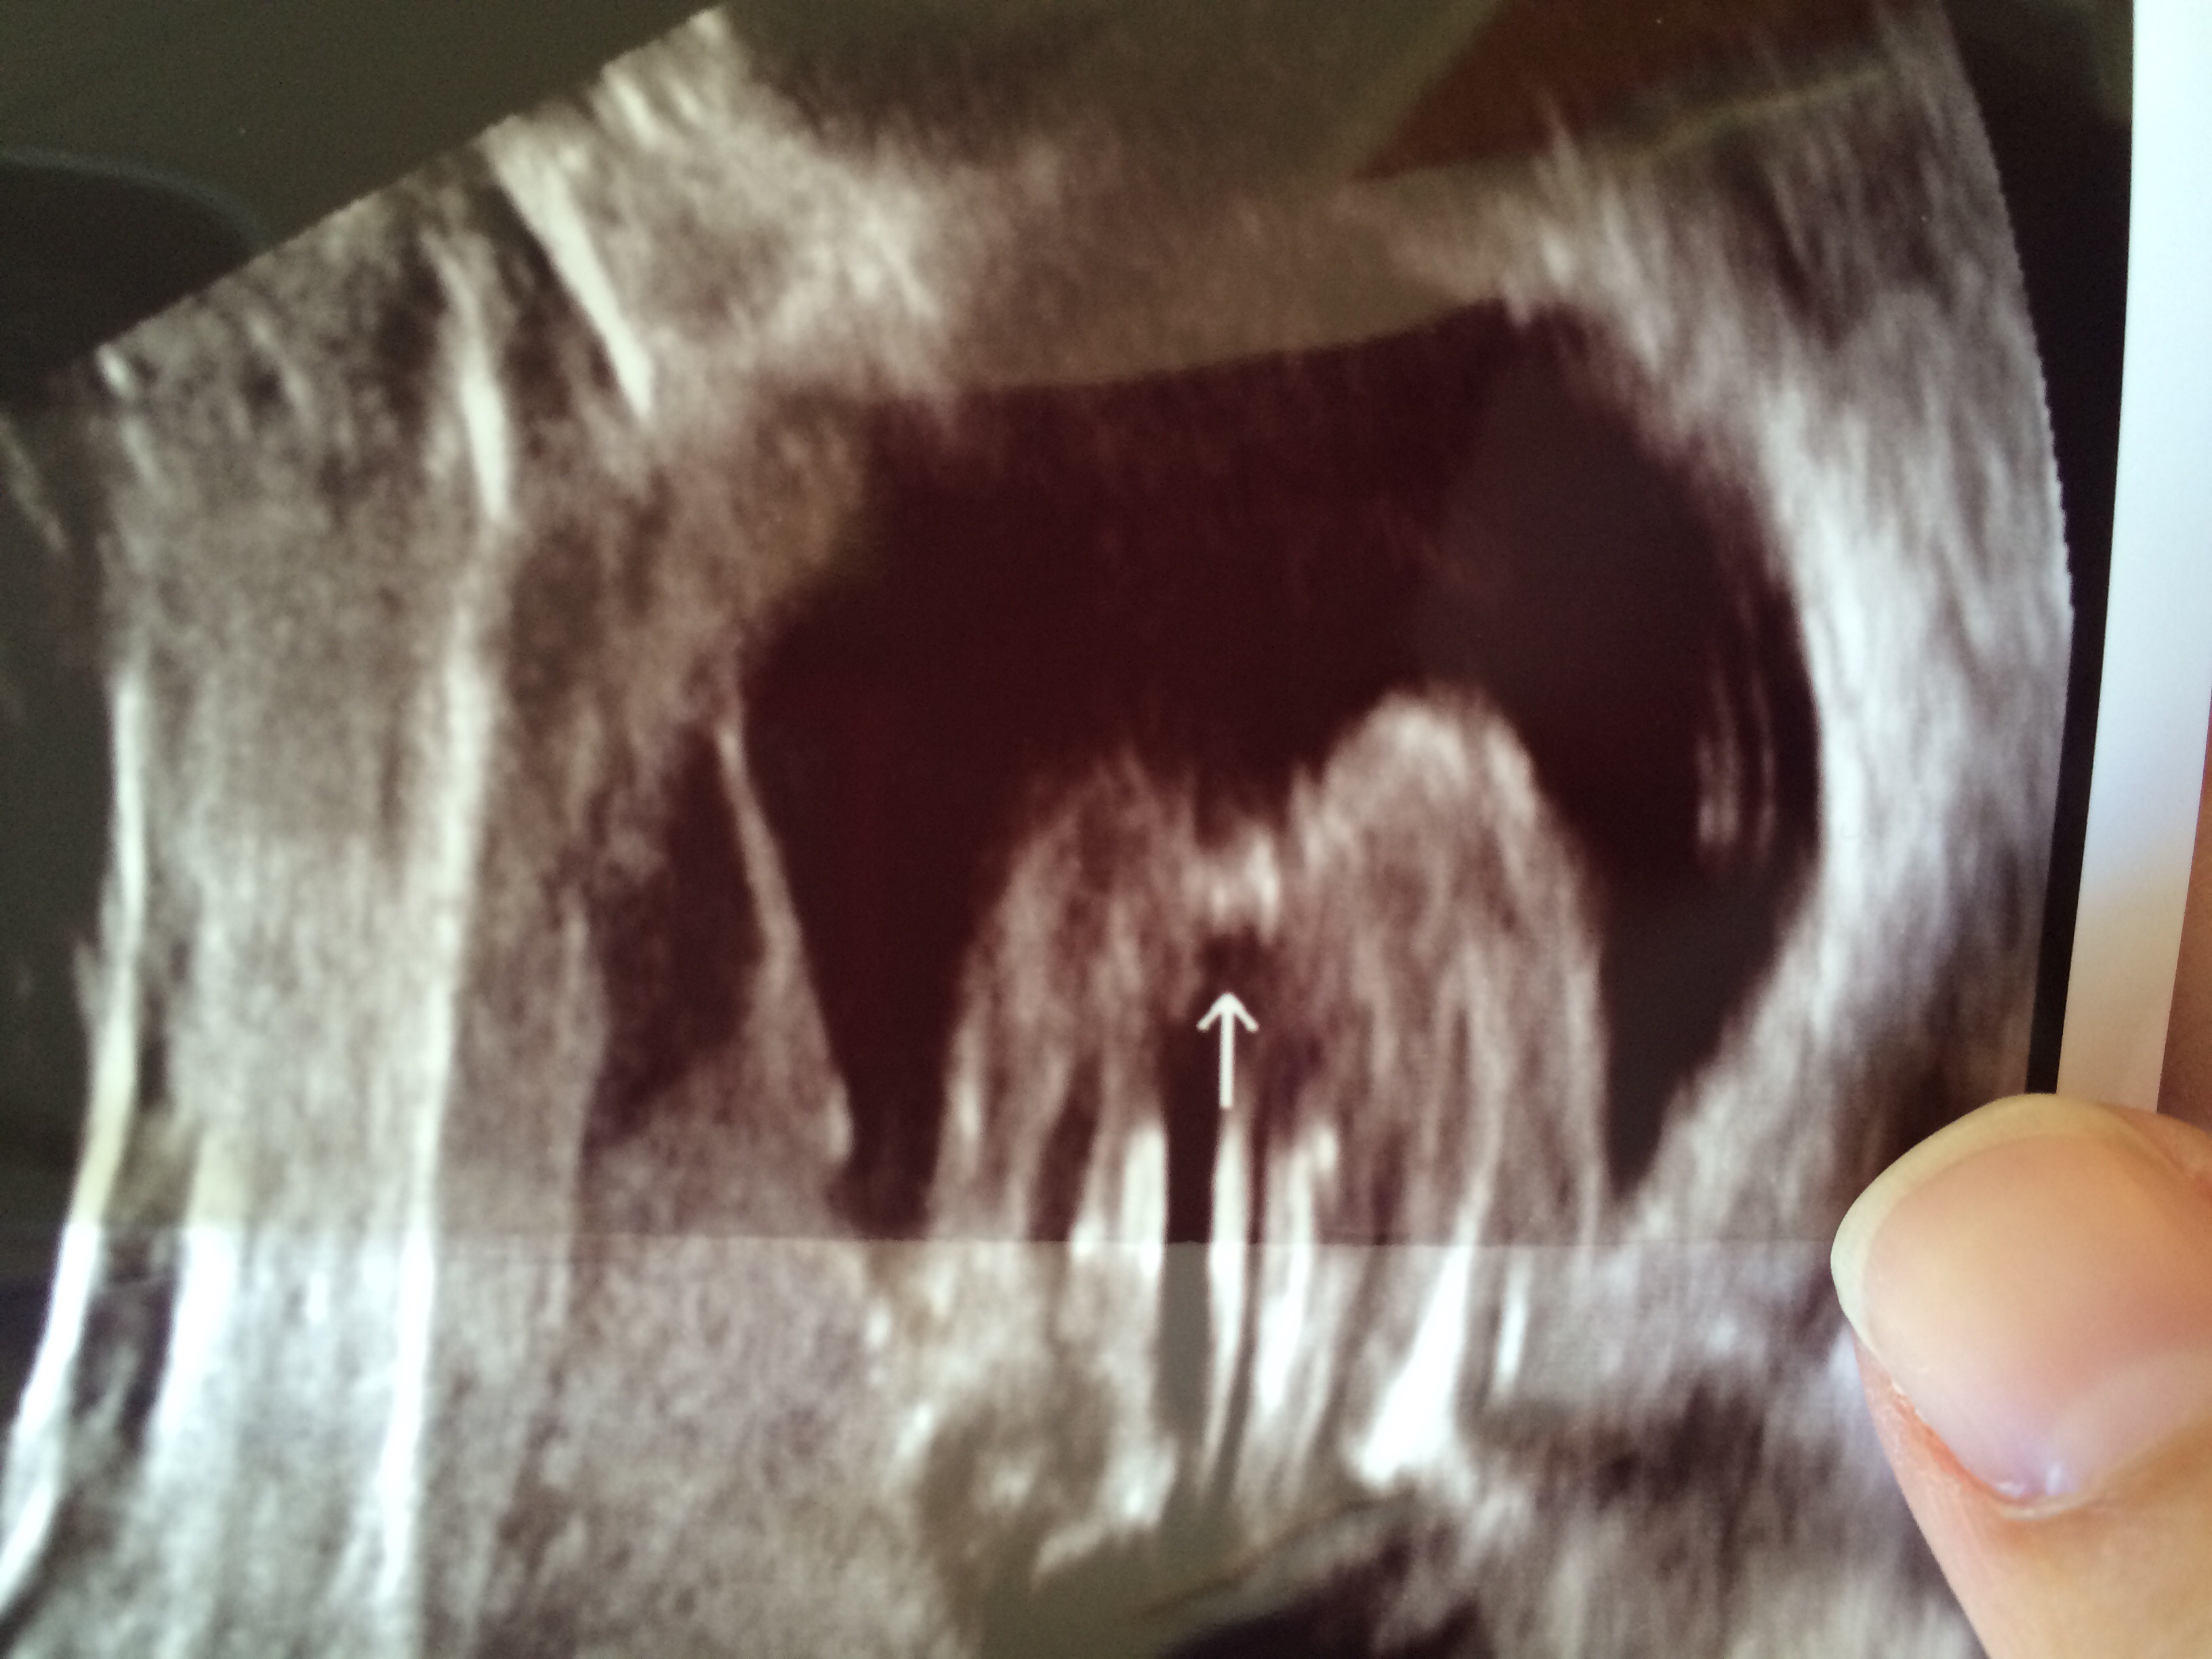

• I would def say girl here's my boy u/s

• I say girl. Here's a pic of my boy at 16wks - pic taken from the bottom up ; )

• You would know for sure if it was a boy. They have a turtle. There is no turtle on your daughter.

I'm expecting son #2, and both boys were for sure a boy, with their turtles hanging out for all to see.